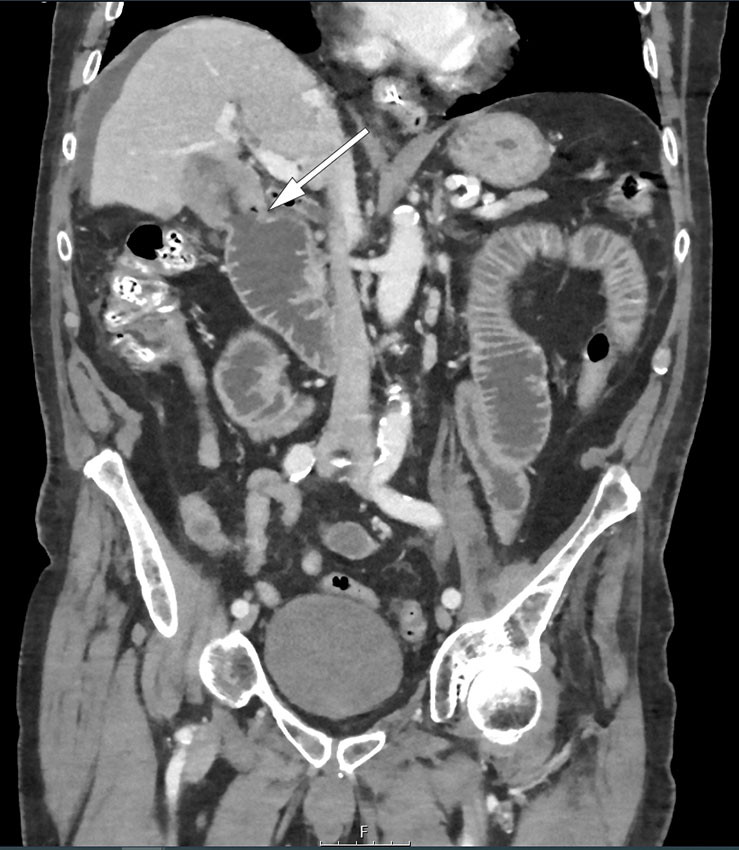

Ultralyd viste metastasesuspekte forandringer i lever. Supplerende CT viste en malignitetssuspekt oppfylning svarende til galleblæren og flere mindre lesjoner i leverparenkymet. Man så også en bred fistel mellom galleblæren og duodenum samt distenderte tynntarmsslynger i øvre abdomen. Bekkenet var ikke inkludert i den første CT-undersøkelsen, og nivå for eventuelt passasjehinder ble ikke fremstilt. Pasienten ble overflyttet til kreftavdelingen for å ta biopsi.

Ved tilsyn var pasienten i god allmenntilstand, med normale vitale parametere, men klaget over magesmerter. Abdomen var utspilt, myk og lett, diffust øm ved palpasjon. Det ble lagt nasogastrisk sonde, med god effekt på smertene. Ny CT viste ileus med rotasjonstendens i krøset og kaliberveksling sentralt i tynntarmen. Galleblærekonkrementet ble imidlertid ikke identifisert ved første granskning. Orienterende blodprøver preoperativt, inkludert lever- og galleprøver, viste nå normale funn, med unntak av CRP 121 mg/L (< 5). Det ble funnet indikasjon for laparotomi, og piperacillin 4 g / tazobaktam 0,5 g × 4 intravenøst ble gitt grunnet risikoen for bakteriell translokasjon.

Vår pasient hadde et ikke-røntgentett konkrement som knapt lot seg avbilde på CT. Ultralyd viste et tydelig skyggegivende konkrement, og i lys av ultralydfunnet kunne man så vidt skimte konturen av dette på røntgen oversikt abdomen. Ved ny granskning så man også luft i galletreet og kolecystoduodenal fistel på CT (figur 2). På CT-bilder fra fire år tidligere kunne man ane et stort konkrement i galleblæren, men ingen fistel eller tumor.